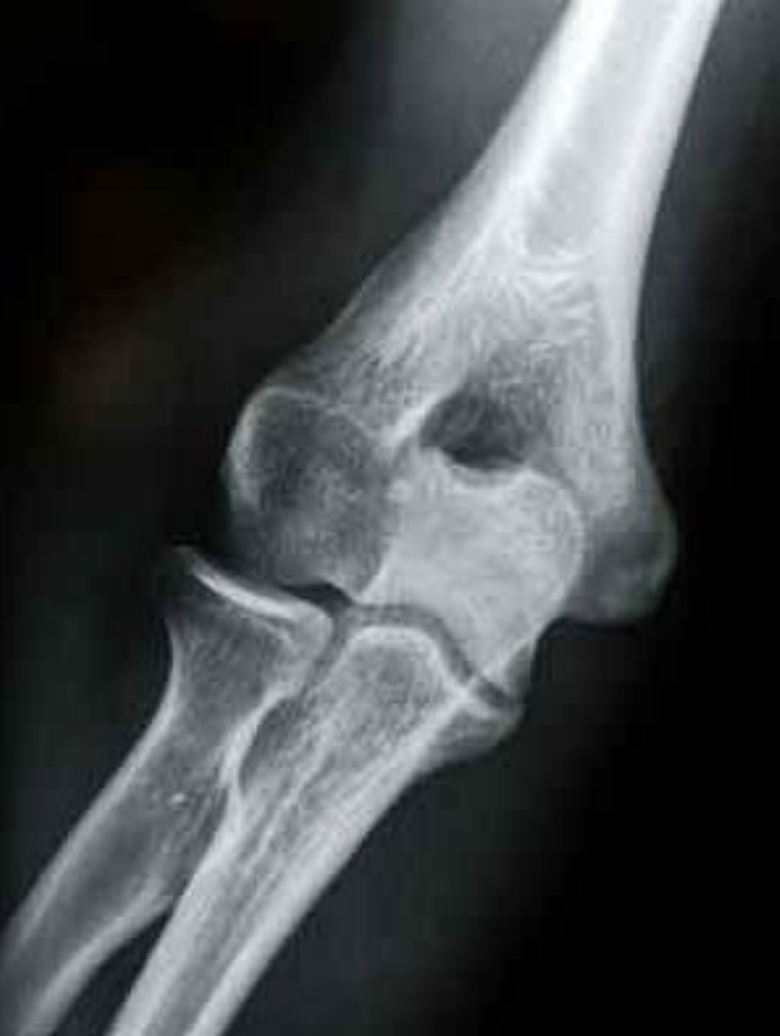

What is this view in the elbow? What views are missing?

– AP

MISSING:

– Lateral Flexion

– Medial Oblique

– +- supination or pronation AP